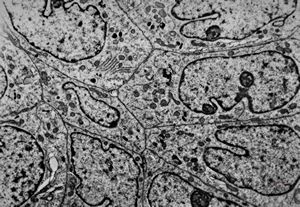

rabbit spinal cord trauma